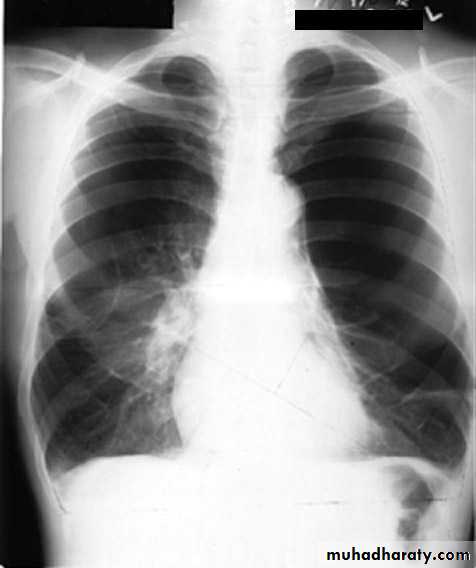

Bronchopneumonia